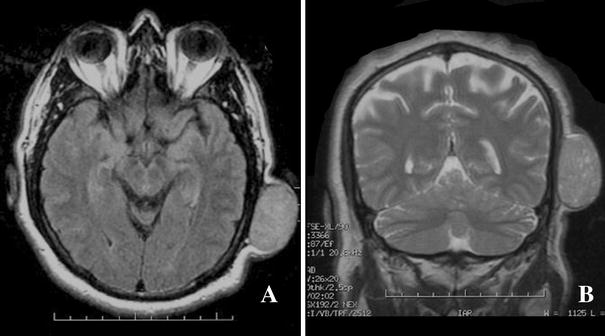

The mass was evaluated by both computed tomography (CT) and magnetic resonance (MR). On CT, the mass was clearly identified and noted not to have an calvarial involvement. By MR imaging, the mass was relatively isointense on T1 weighted images, slightly bright on T2 weighted images with flow voids (Fig. 2). On both MR and CT, the presence of significant left-sided cervical adenopathy was evident. A PET scan was also obtained which showed abnormal uptake at the left posterior scalp and mid-left lower neck. No distant lesions were identified.

Fig. 2

Axial T1 (a) and coronal T2 (b) MR images of the left parietal scalp mass